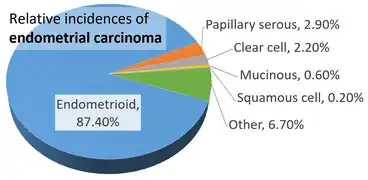

Endometrioid carcinoma can also arise in the endometrium.[4][5]

Relative incidences of endometrial carcinomas by histopathology, being endometrioid in a majority of cases[7]

Relative incidences of endometrial carcinomas by histopathology, being endometrioid in a majority of cases[7]